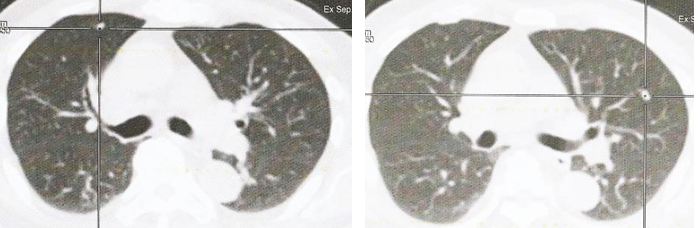

There are multiple small lung nodules scattered in both lungs,

largest measuring up  to 0.8 x 0.7 cm at the right lung base.

2. Multiple bilateral lung nodules – suspicious for lung metastases.

• No focal FDG-avid lesions in the head and neck region,  lung parenchyma lesions, chest wall lesions, mediastnal nodes or hilar masses.

GT went back to the TCM  hospital again. She did a CT scan. The lump in her breast had grown bigger, to 3.8 x 1.8 cm. The cancer had spread to her lungs and bone. Unfortunately, GT did not bring along her CT scan so I am not able to see the extent of her metastasis.

3. Now, the cancer has already spread to your lungs and bone. I don’t know how extensive it is because you did not bring along your CT scan.